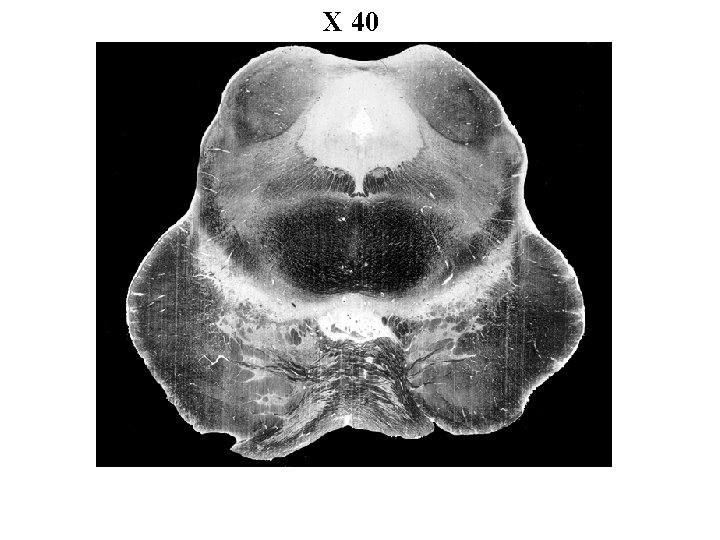

X 40